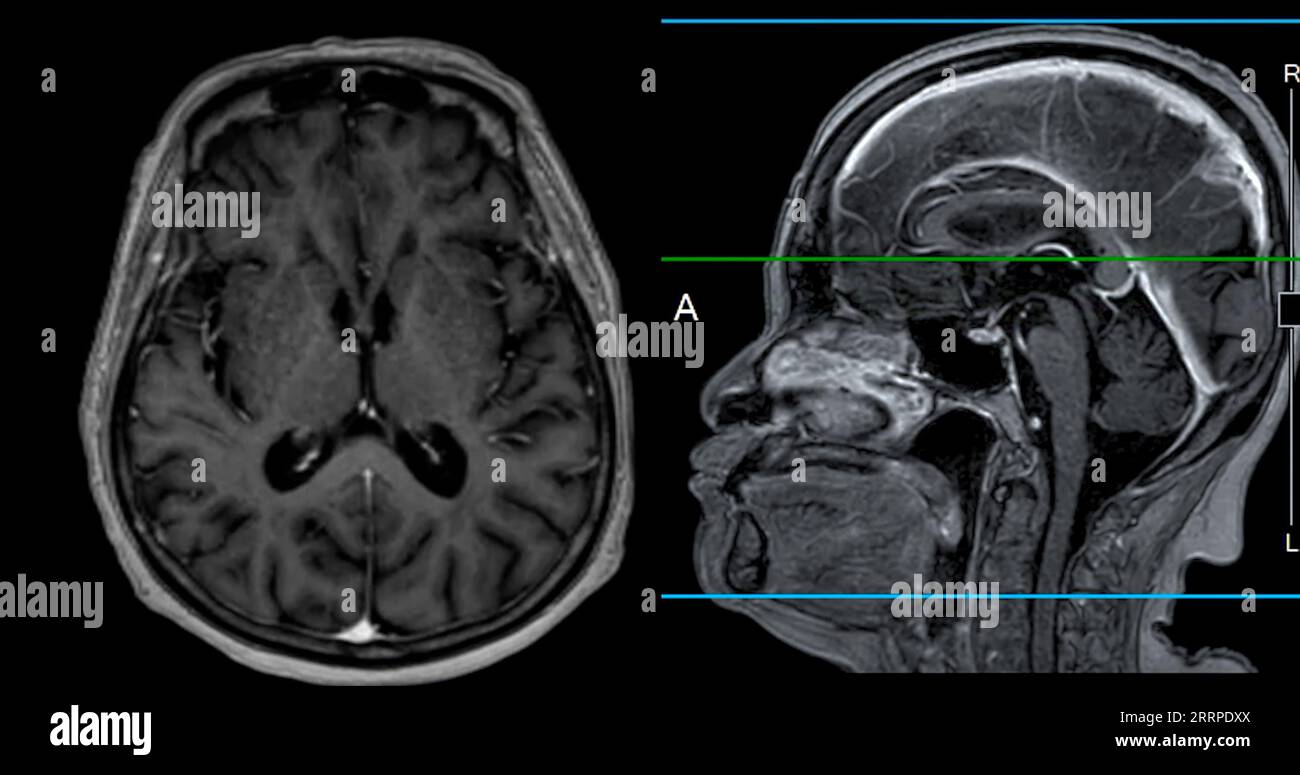

From www.alamy.com

MRI brain scan Axial and sagittal view with reference line for detect What Can Brain Mri Detect That Ct Cannot Bones, stones, blood, organs, lungs, cancer stages and abdominal emergencies. Ct scans are the most common. A variant called mr angiography (mra). An mri scan can be used to examine almost any part of the body, including the: Internal organs, such as the liver, womb. Where mri really excels is showing certain diseases that a ct scan cannot detect. Some. What Can Brain Mri Detect That Ct Cannot.

MRI brain scan Axial and sagittal view with reference line for detect What Can Brain Mri Detect That Ct Cannot A variant called mr angiography (mra). In the case of brain imaging, mri provides highly accurate and detailed images of the human brain, allowing healthcare professionals to assess its anatomy and detect any abnormalities. Some cancers, such as prostate cancer, uterine cancer, and certain liver cancers, are pretty much. Internal organs, such as the liver, womb. Bones, stones, blood, organs,. What Can Brain Mri Detect That Ct Cannot.

From pubs.rsna.org